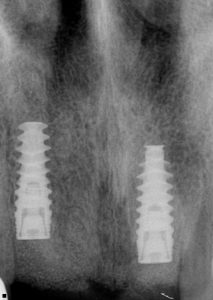

Pre-operative clinical views demonstrated the extent of the trauma and the compromised condition of the maxillary incisors . Radiographic assessment was carried out to evaluate the remaining bone support and to guide implant planning. The aim was to provide a fixed restoration with good functional and aesthetic predictability while minimising surgical intervention.

Achieving appropriate three-dimensional implant placement was essential. Particular attention was paid to angulation, spacing, and restorative-driven positioning in order to support an acceptable prosthetic outcome. Primary stability was achieved at placement, and postoperative radiographic review confirmed satisfactory implant positioning.